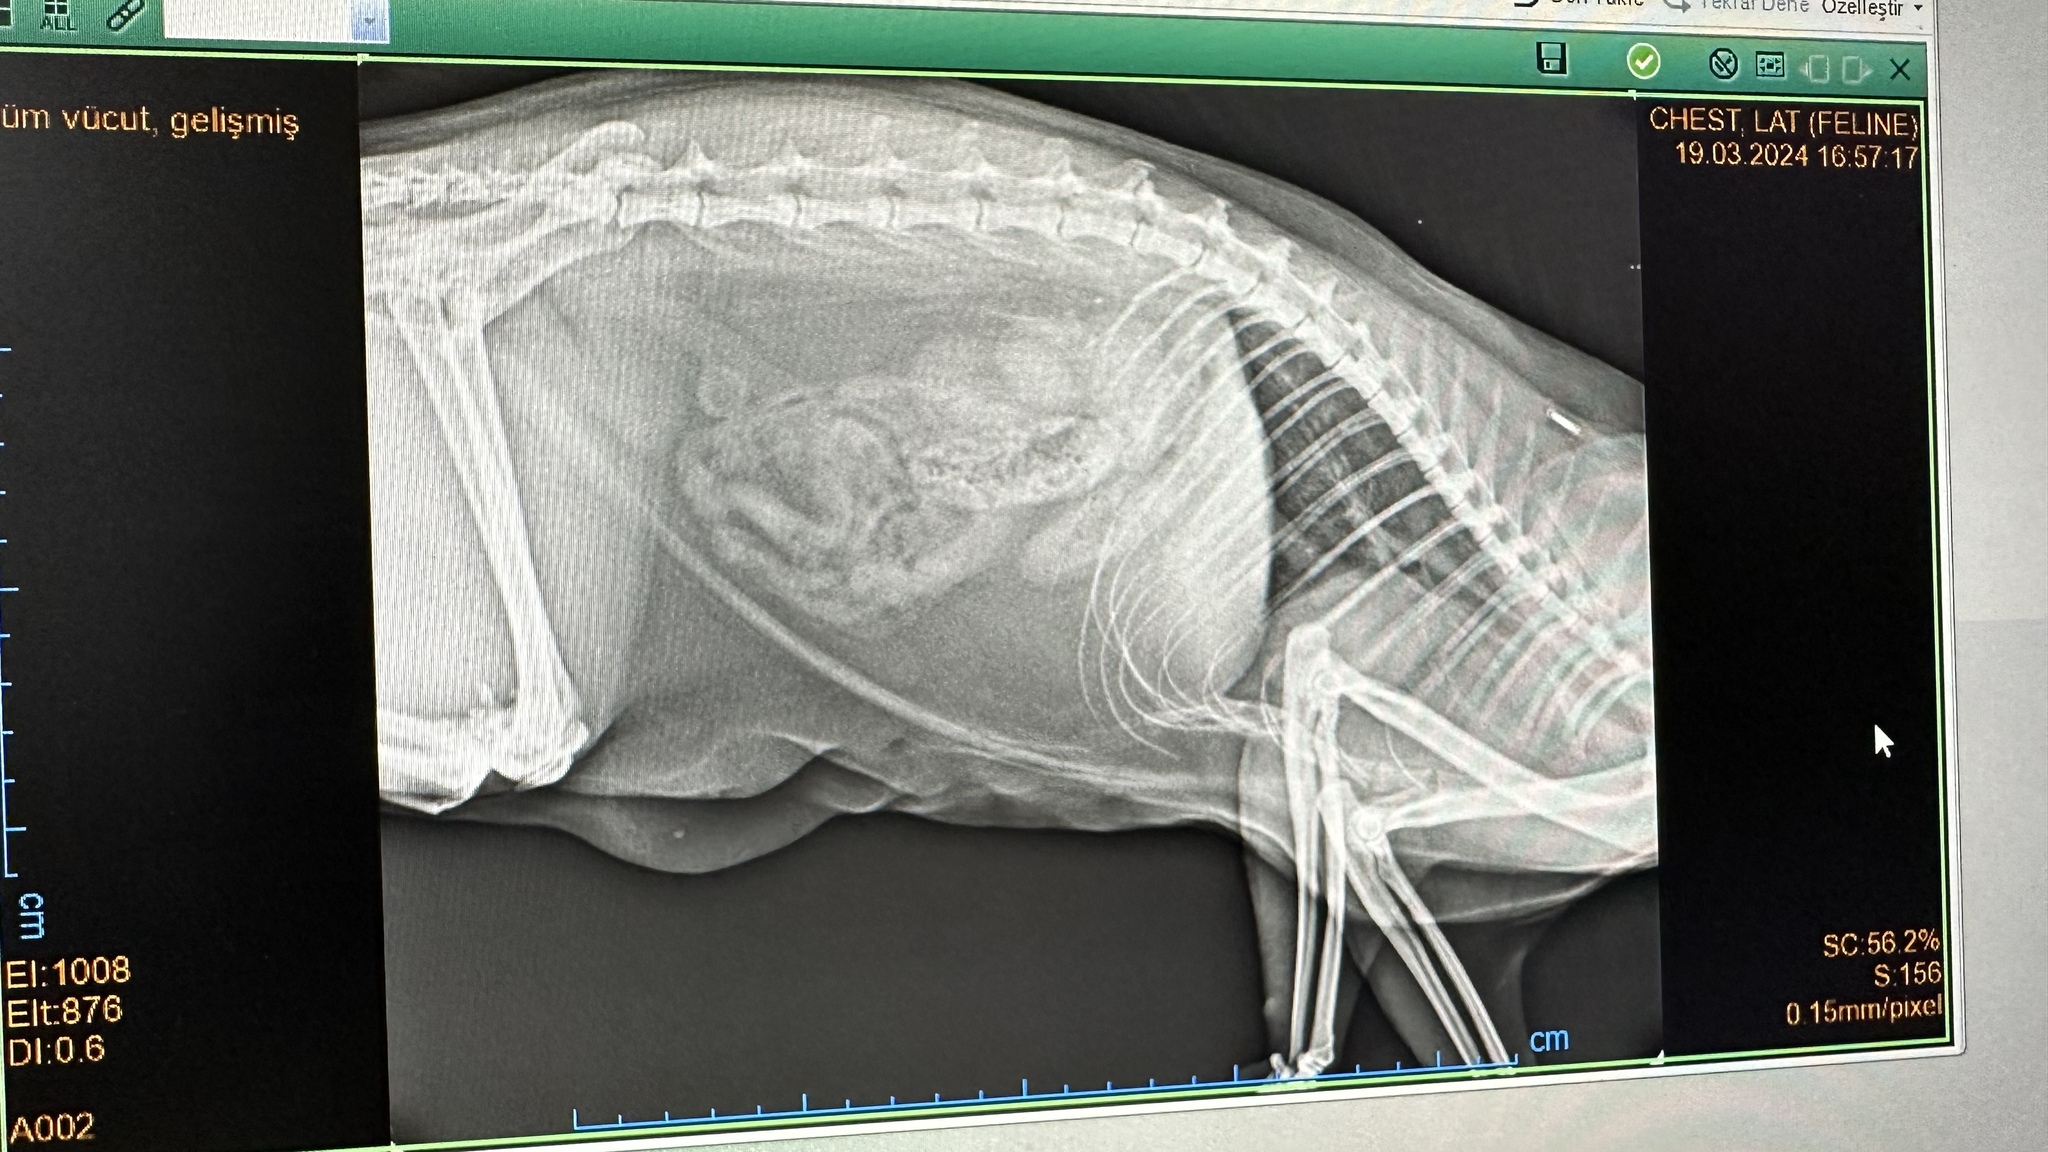

Коту три года. В 2022 увидели, что кот кашляет, как будто комок шерсти срыгивает, но не может. Такое явление повторялось редко, может, раз в несколько месяцев. Но сейчас интервал между такими приступами уменьшился. Когда первый раз ходили к ветеринару с этой проблемой, сказал, что ничего страшного. (территориально находимся в Турции, обращаемся к местным докторам). Сегодня отнесли кота к другому ветеринару, она сделала только рентген, сказала, что увеличено сердце, левая почка и грибок в лёгких. Выписала: Semitra (1мл/1кг веса), экстракт калины и Royal Canin Urinary. Пить семь дней, потом снова на рентген.